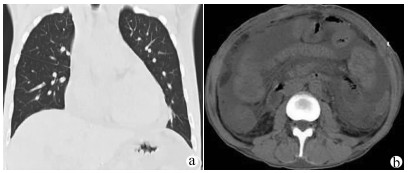

Viridans streptococci sepsis with liver abscess and hepatic vein thrombosis: A case report

Abstract(986) HTML (427) PDF (2002KB)(59)

Abstract: